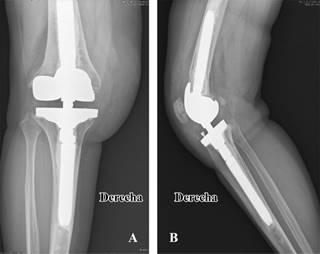

Una vez planificados los cortes mediante las guías femorales y tibiales, se decide el tamaño protésico y la utilización de cuñas adicionales en defectos óseos asimétricos (Figura 1). Todos los componentes tibiales como los femorales son cementados, y en el total de pacientes se realiza rótula protésica.

Figura 1: Radiografías anteroposterior (A) y lateral (B). Cirugía de revisión mediante prótesis bisagra rotatoria en paciente con inestabilidad previa. Adición de cuñas femorales tras defecto femoral asimétrico.